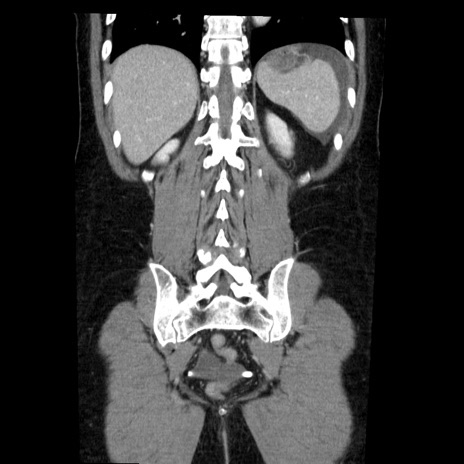

症例6(冠状断像)

【症例】50歳代女性

【主訴】下腹部痛

【既往歴】卵巣癌術後(8年前に当院で卵巣摘出)

【身体所見】 意識清明、腹部:平坦、腸蠕動音→、やや硬、下腹部自発痛・圧痛あり、反跳痛あり、筋性防御なし。

【データ】WBC 16000、CRP 0.01